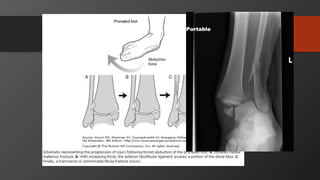

Ankle Fractures

Imaging

• AP, Lateral

• Mortise view

• CT scan

• Especially posterior malleolus

Initial treatment- reduce dislocations